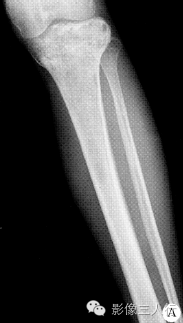

• 【病例】左胫骨弥漫性非霍奇金淋巴瘤1例X线MR影像表现

【病例】左胫骨弥漫性非霍奇金淋巴瘤1例X线MR影像表现